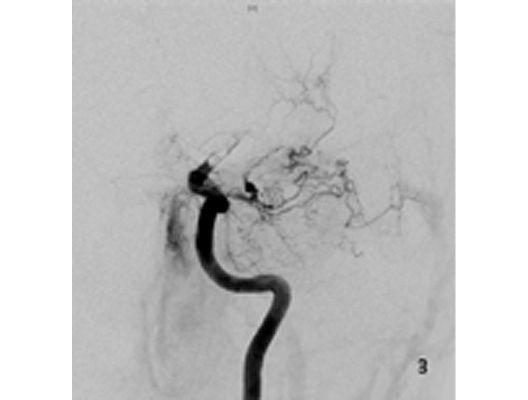

Angiographie: Behandlung von Aneurysmen

Behandlung von Aneurysmen

Aneurysmen an der Gefäßen des Gehirns können in vielen Fällen minimalinvasiv durch einen Zugang durch das Gefäßsystem, zumeist von der Leiste aus behandelt werden (sog. Endovaskuläre Therapie). Dabei gibt es z.B. die Möglichkeit ein Aneurysma durch Einbringung von Platinspiralen zu verschließen (sog. Coiling). Auch für komplexe Aneurysmen stehen inzwischen verschiedene endovaskuläre Methoden zur Verfügung.

Das Beispiel zeigt die angiographischen Bilder einer Patientin, bei der es zu einer Sehstörung gekommen war. Die Ursache war ein großes Aneurysma der Halsschlagader an der Schädelbasis (Bild 1). Bild 2 zeigt die Lage des Aneurysmas hinter dem Auge. Durch den Druck des Aneurysmas auf den Sehnerv war es zu der Sehstörung gekommen. Die Patientin wurde mit einer speziellen Gefäßprothese versorgt, welche über eine Punktion der Leistenarterie in die Halsschlagader eingesetzt wurde (Bild 3). Bei der Kontrolle nach 6 Monaten zeigte sich ein vollständiger Verschluss des Aneurysmas (Bild 4). Die Sehstörung hatte sich vollständig zurückgebildet.